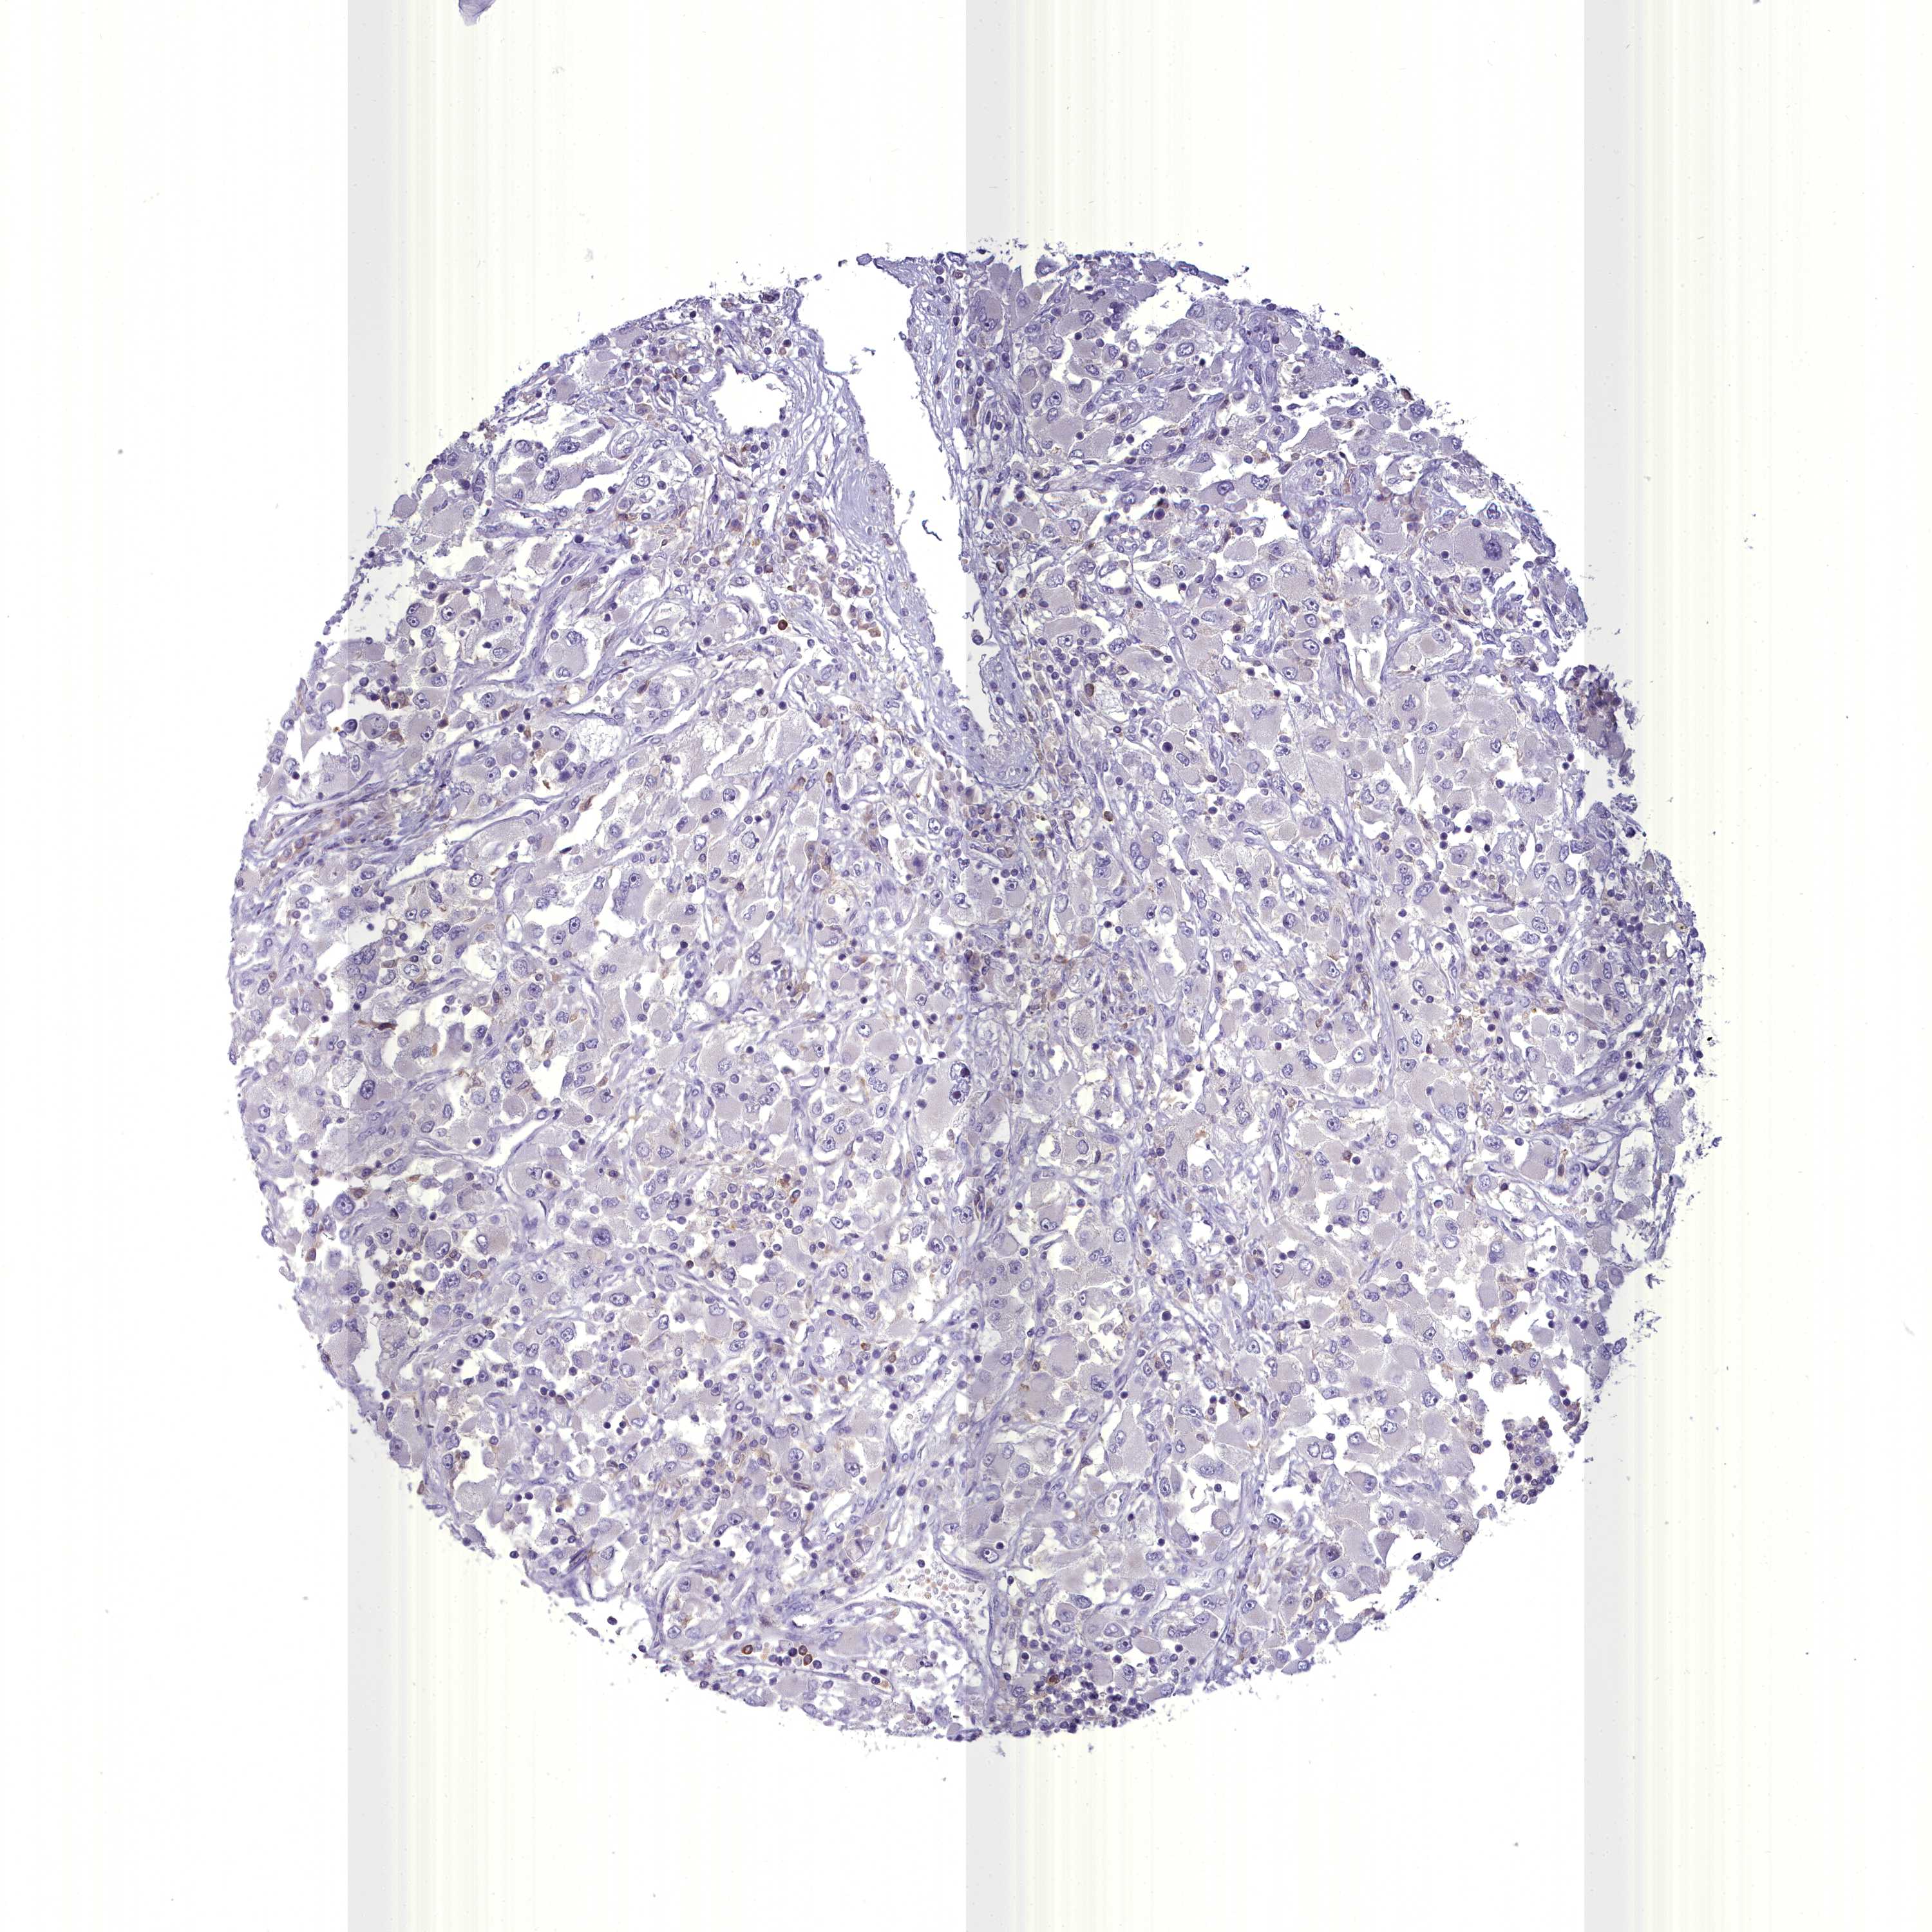

KIDNEY RENAL CLEAR CELL CARCINOMA (VALIDATION) - Interactive survival scatter ploti

BLNK is not prognostic in Kidney Renal Clear Cell Carcinoma (validation)

: 15.53

Average pTPM 14.3

Number of samples 100